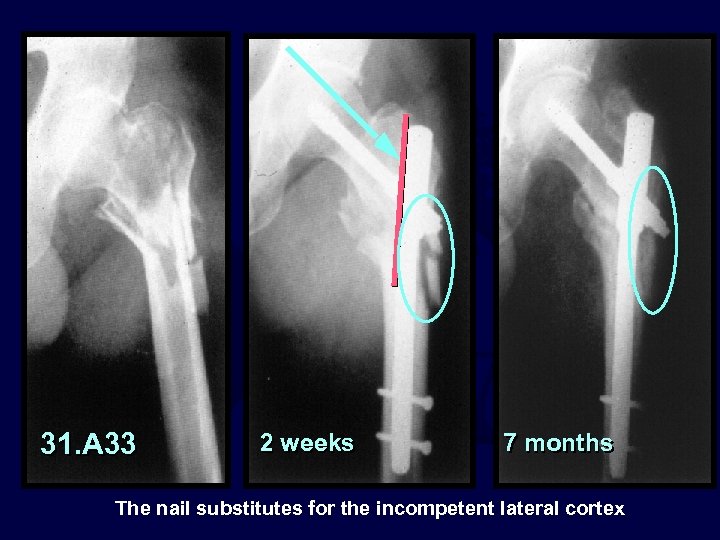

The nail substitutes for the incompetent posteromedial cortex

31. A 33 2 weeks 7 months The nail substitutes for the incompetent lateral cortex